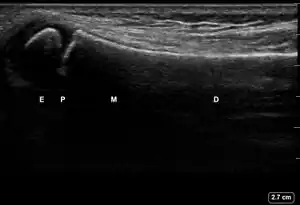

| 3 | Cortical Break Fracture | "Broken" | Break, step or gap in bone cortex which appears as a black zone in the bright, sharp white line[10][11][14][15][16] | ![]() Ultrasound dorsal view of cortical break fracture of radius (shown by arrow). E = epiphysis; P = physis; M = metaphysis; D = diaphysis. |

| 1 | Angulation of the distal bone segment[14] | ![]() Ultrasound view of angulation of distal bone segment (shown by arrow). E = epiphysis; P = physis; M = metaphysis; D = diaphysis. | |